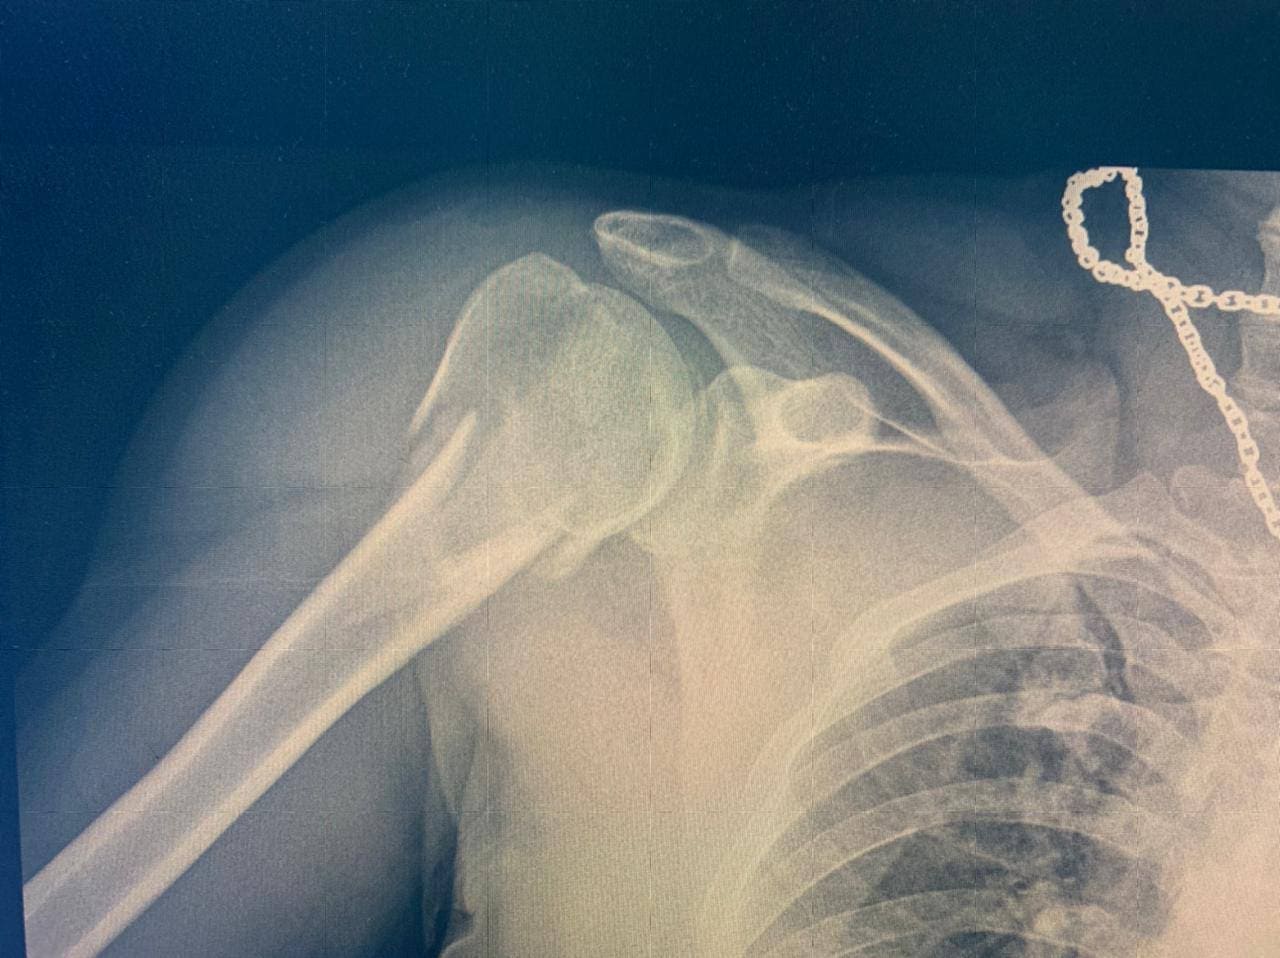

Лечение перелома плеча

Перелом плеча - это повреждение кости верхней части руки (плечевой кости), которое происходит при наличии достаточной силы, направленной на плечевой пояс. Перелом плеча может произойти в результате падения на вытянутую руку, удара в плечо или в результате аварии на дороге.

Перелом плеча может быть различной степени тяжести, в зависимости от того, какая часть кости была повреждена и насколько серьезно. Для лечения переломов плеча могут применять как хирургические, так и консервативные методы лечения.

• Рентген – один из самых распространенных методов диагностики переломов плеча. Рентгеновские лучи помогают врачу увидеть внутреннюю структуру костей и определить наличие перелома;